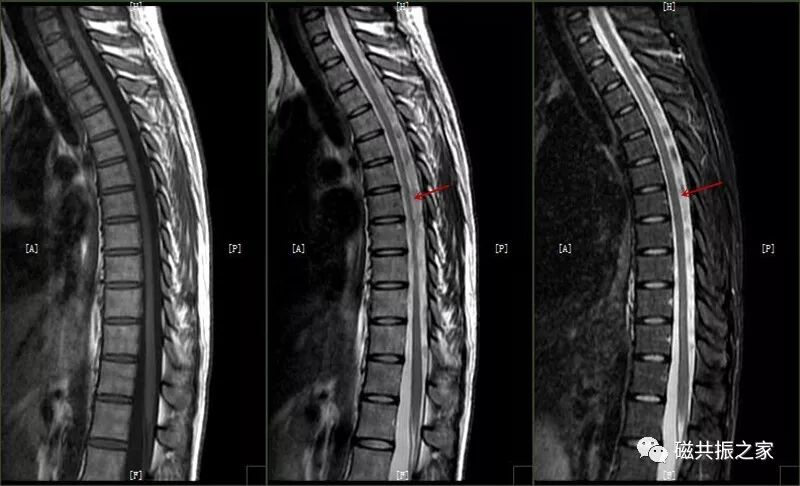

脑脊液流动伪影常易误诊为病变,需与椎管内占位相鉴别。如脊髓背侧脑脊液中可见多个不连续的低信号区,在不同序列成像中表现不同,有时可通过梯度回波 T2 加权像消除此伪影。

截断伪影常见于 MR 信号强度突然变化的组织界面,如脂肪-肌肉和脊髓-脑脊液界面,可能导致脊髓内出现虚假高信号,易被误解为脊髓空洞或损伤。通过校正编码方向等方法可改善。

蓝色箭头所指的是由脊髓腔内脑脊液流动所形成的流动伪影,白色箭头所指的则是截断伪影。蓝色和白色箭头所呈现的征象均属于伪影,椎管和脊髓实际上是正常的,而星号区域为 L1 椎体血管瘤。